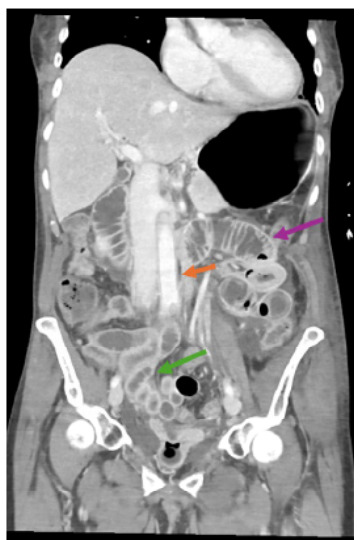

Case report: We present the case of a 64-year-old female with a history of hypertension, hyperlipidemia, and breast cancer who developed acute kidney injury (AKI) and retroperitoneal necrotizing fasciitis following a 20-mile bike ride. The patient's initial symptoms included severe muscle aches, nausea, vomiting, and flank pain. Diagnostic imaging and laboratory results indicated myositis and severe AKI. Despite aggressive treatment with antibiotics, intravenous fluids, and pain management, the patient developed septic shock and multiorgan failure, ultimately leading to her death.